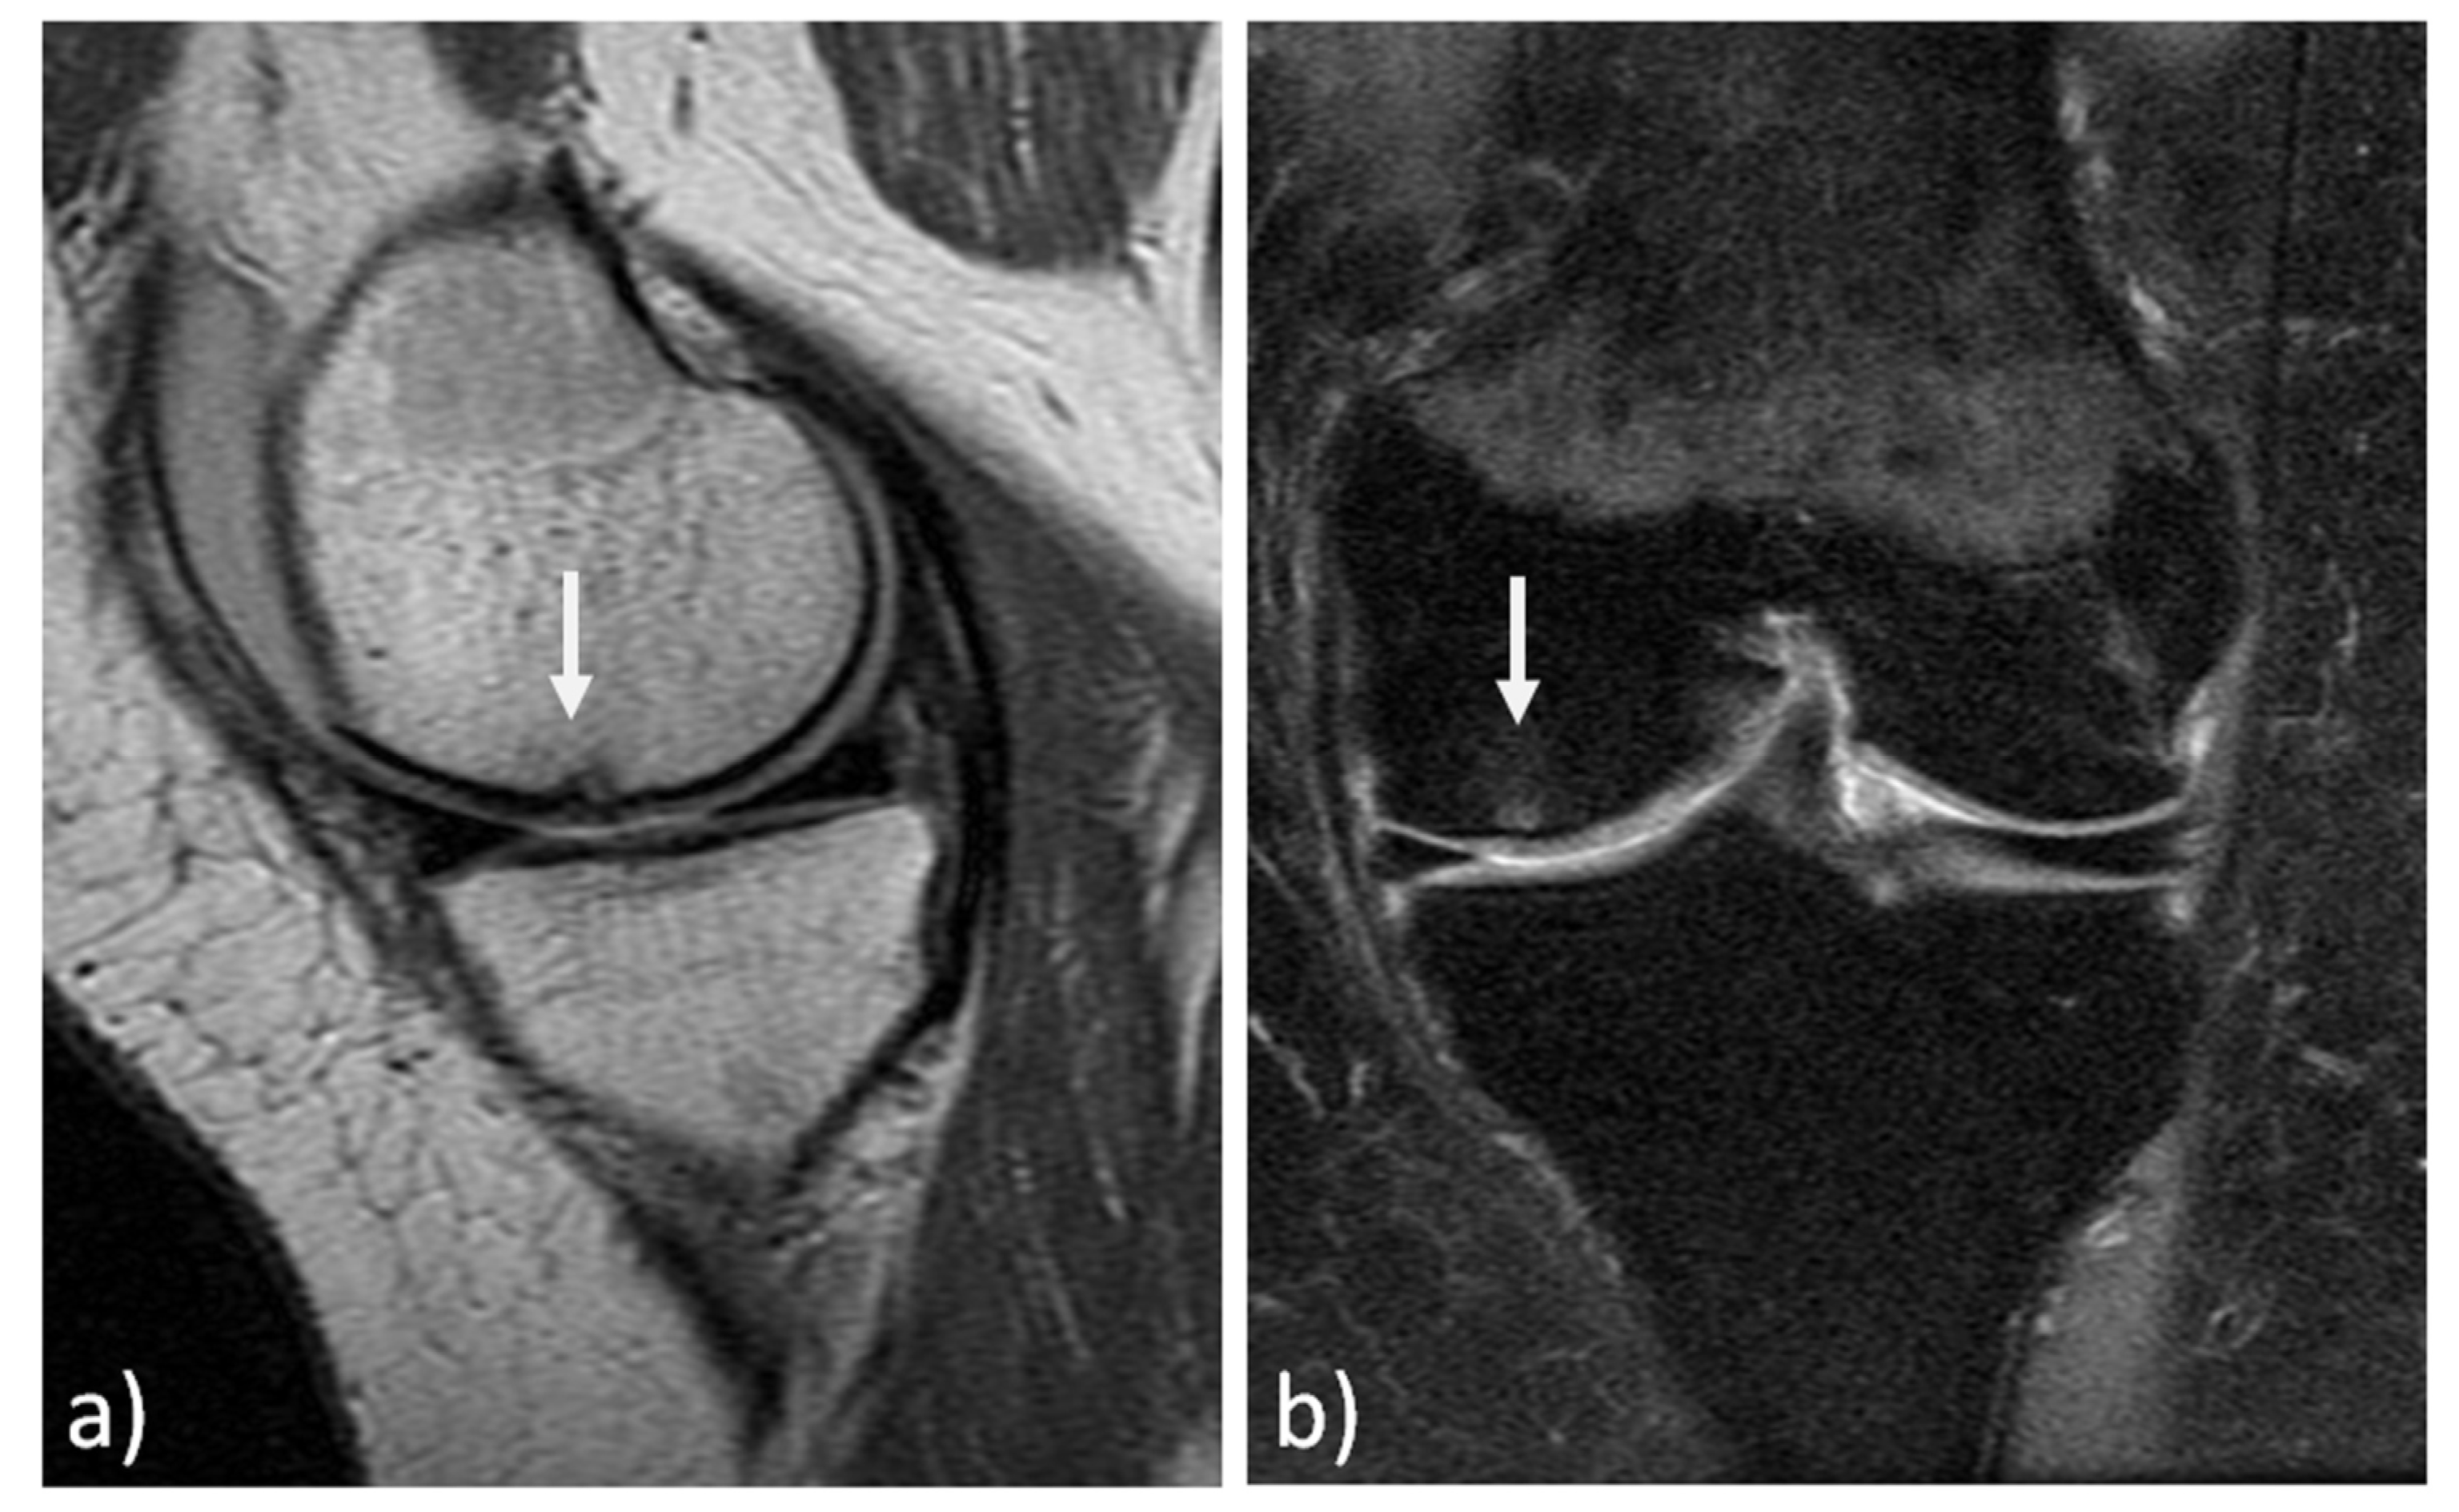

The MRI findings of 30 knees (15 mosaicplasty and 15 MACT), analyzed with the MOCART 2.0 scoring system, showed a high rate of cartilage defect filling in both groups, and a complete integration into the adjacent cartilage in half of the patients in both groups. However, the surface of the repair tissue was damaged in the majority of cases. The structure of the repair tissue was homogeneous in most cases, and the signal intensity was normal (isointense) in half of the patients in both groups. At subchondral bone level, a bony defect or bony overgrowth was reported in the majority of patients, while an edema-like marrow signal was reported in almost half of the patients in both groups (Figure 3 and Figure 4). No significant differences were reported between the two groups in the overall MOCART 2.0 scores and in all the seven subscales (Table 2).

Figure 3. MRI evaluation at 11 years’ follow-up of a medial femoral condyle lesion treated with mosaicplasty in a 37-year-old man. Sagittal 3D "Cube" PD (a) and coronal PD FAT SAT (b) demonstrate a good filling of the defect (arrows) and a complete integration into adjacent cartilage. However, there is an inhomogeneous structure of the repair tissue with adjacent bony overgrowth.